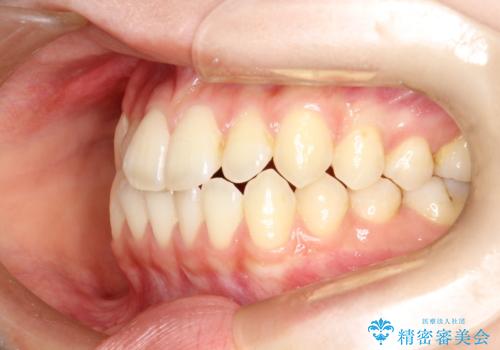

前歯のガタつき、下顎の前突感を治したい インビザライン矯正例

- 治療計画